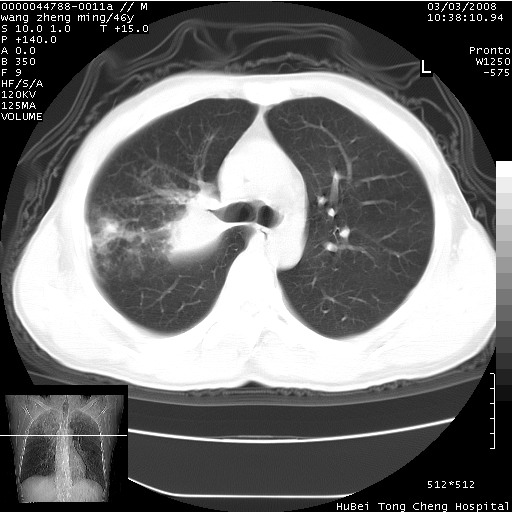

以下是引用卜一在2008-3-22 1:37:00的发言:[br]右肺实质性肿块,边缘不整,明显见毛刺征 分叶征及胸膜凹陷征,右上叶支气管明显变窄,远端散在的片状 斑片状实变影。另:左肺门较大肿块,支气管受累 变窄,远侧见阻塞性肺炎。纵隔内见肿大淋巴结。多考虑:右肺周围性肺癌伴左肺门 纵隔淋巴结转移!